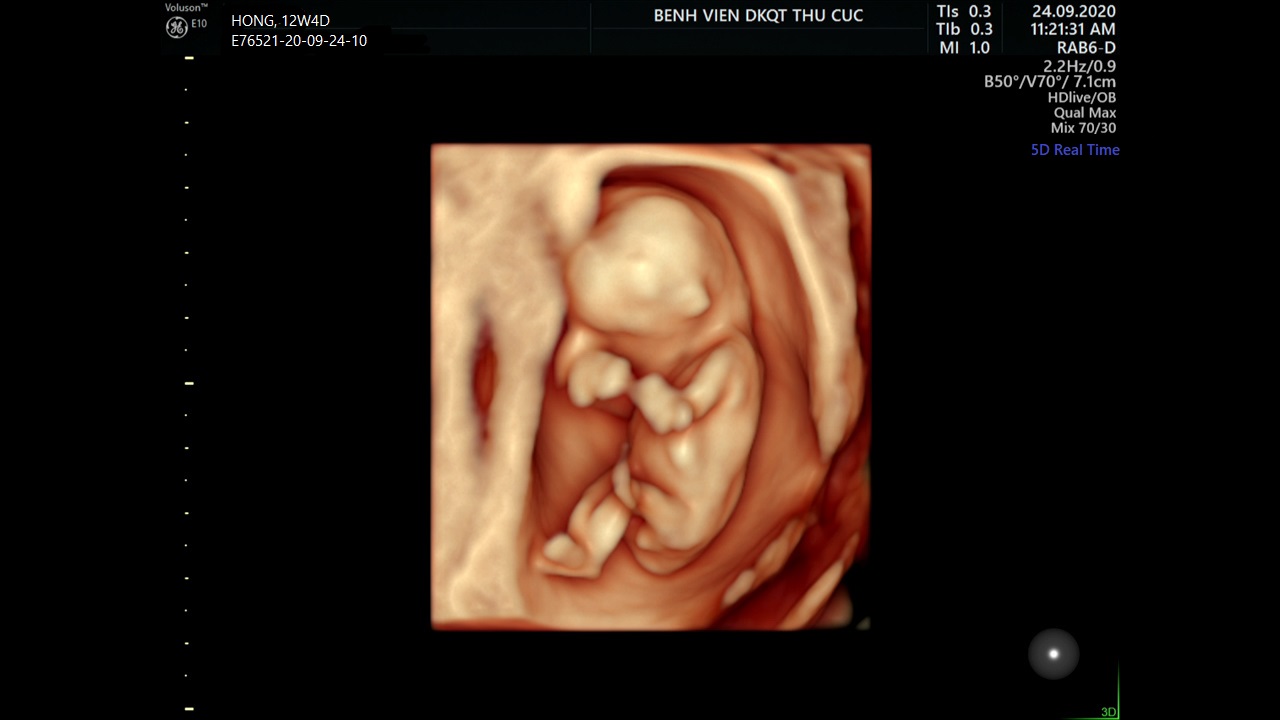

Bước qua 12 tuần đầu mang thai nghĩa là mẹ sắp hoàn thành tam cá nguyệt thứ nhất. Một giai đoạn mới được hình thành với nhiều điều mới mẻ mà mẹ bầu 12 tuần cần lưu ý. Đây là một cột mốc đáng nhớ với nhiều thay đổi về cơ thể mẹ bầu lẫn sự phát triển của thai nhi.

Sự thay đổi của thai nhi

Thai nhi 12 tuần tuổi sẽ có những thay đổi bao gồm:

Chiều dài khoảng 5.3cm, cân nặng khoảng 28g.

Đầy đủ các bộ phận và hệ cơ quan, cơ thể tiếp tục phát triển nhanh chóng.

Dần hoàn chỉnh hơn, xương cứng cáp, hệ thống thần kinh trong não phát triển đáng kể.

Tim thai đập nhanh, có thể gấp đôi nhịp tim của mẹ bầu.

Các ngón tay chân tách rời nhau, bắt đầu có vân tay. Bé hình thành hoạt động co ngón tay, ngón chân.

Miệng có phản xạ mút, mắt vẫn chưa mở.

Hệ tiêu hóa phát triển tương đối hoàn chỉnh, thận bắt đầu làm việc.